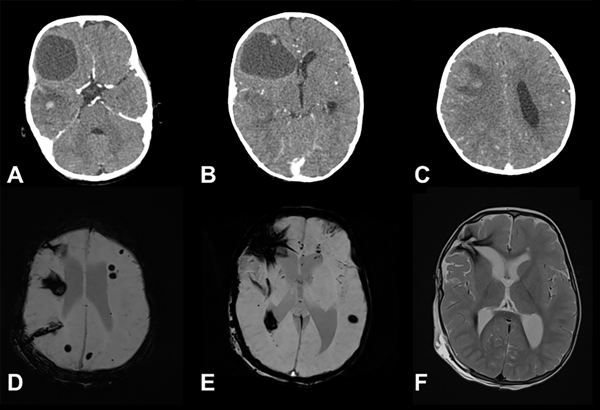

Figura 7. SMCCF. Paciente masculino de 12 meses que ingresa por cuadro de estatus convulsivo. Ingresa a cirugía de urgencia para resección de lesión temporal. Por persistir con crisis se realiza reexploración y exéresis de lesión frontal, tras lo cual controla las adecuadamente. A-C) TC cerebral con contraste EV que muestra dos lesiones hemorrágicas extensas en distintos estadios. Lesión temporal derecha subaguda, frontal derecha quística en reabsorción. D) y E) RM de cerebro secuencia SWI que pone de manifiesto múltiples lesiones, efecto “blooming” de distintos tamaños corticosubcorticales y profundas. F) Lesiones negativas en la secuencia T2.

En nuestra serie, uno de los pacientes con SMCCF (ver Figura 7) ingresó por estatus convulsivo, por lo que fue intervenido de urgencia resecando una lesión temporal. Sin embargo, al persistir las crisis en el postoperatorio, se lograron controlar tras resección de lesión frontal.